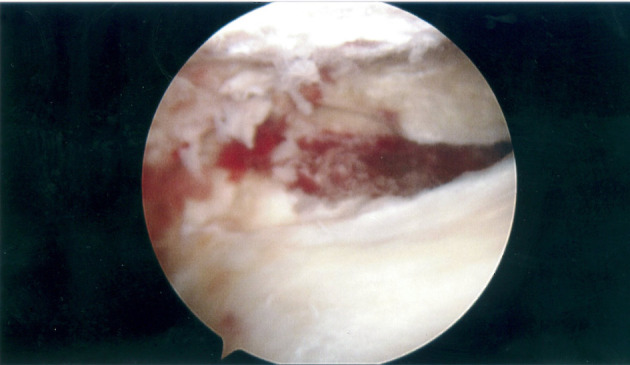

Figure 7.

Arthroscopic view of left knee showing haemarthrosis and flap of lateral meniscal tissue.

Figure 8.

Arthroscopic view of left knee showing horizontal tear in lateral meniscus.